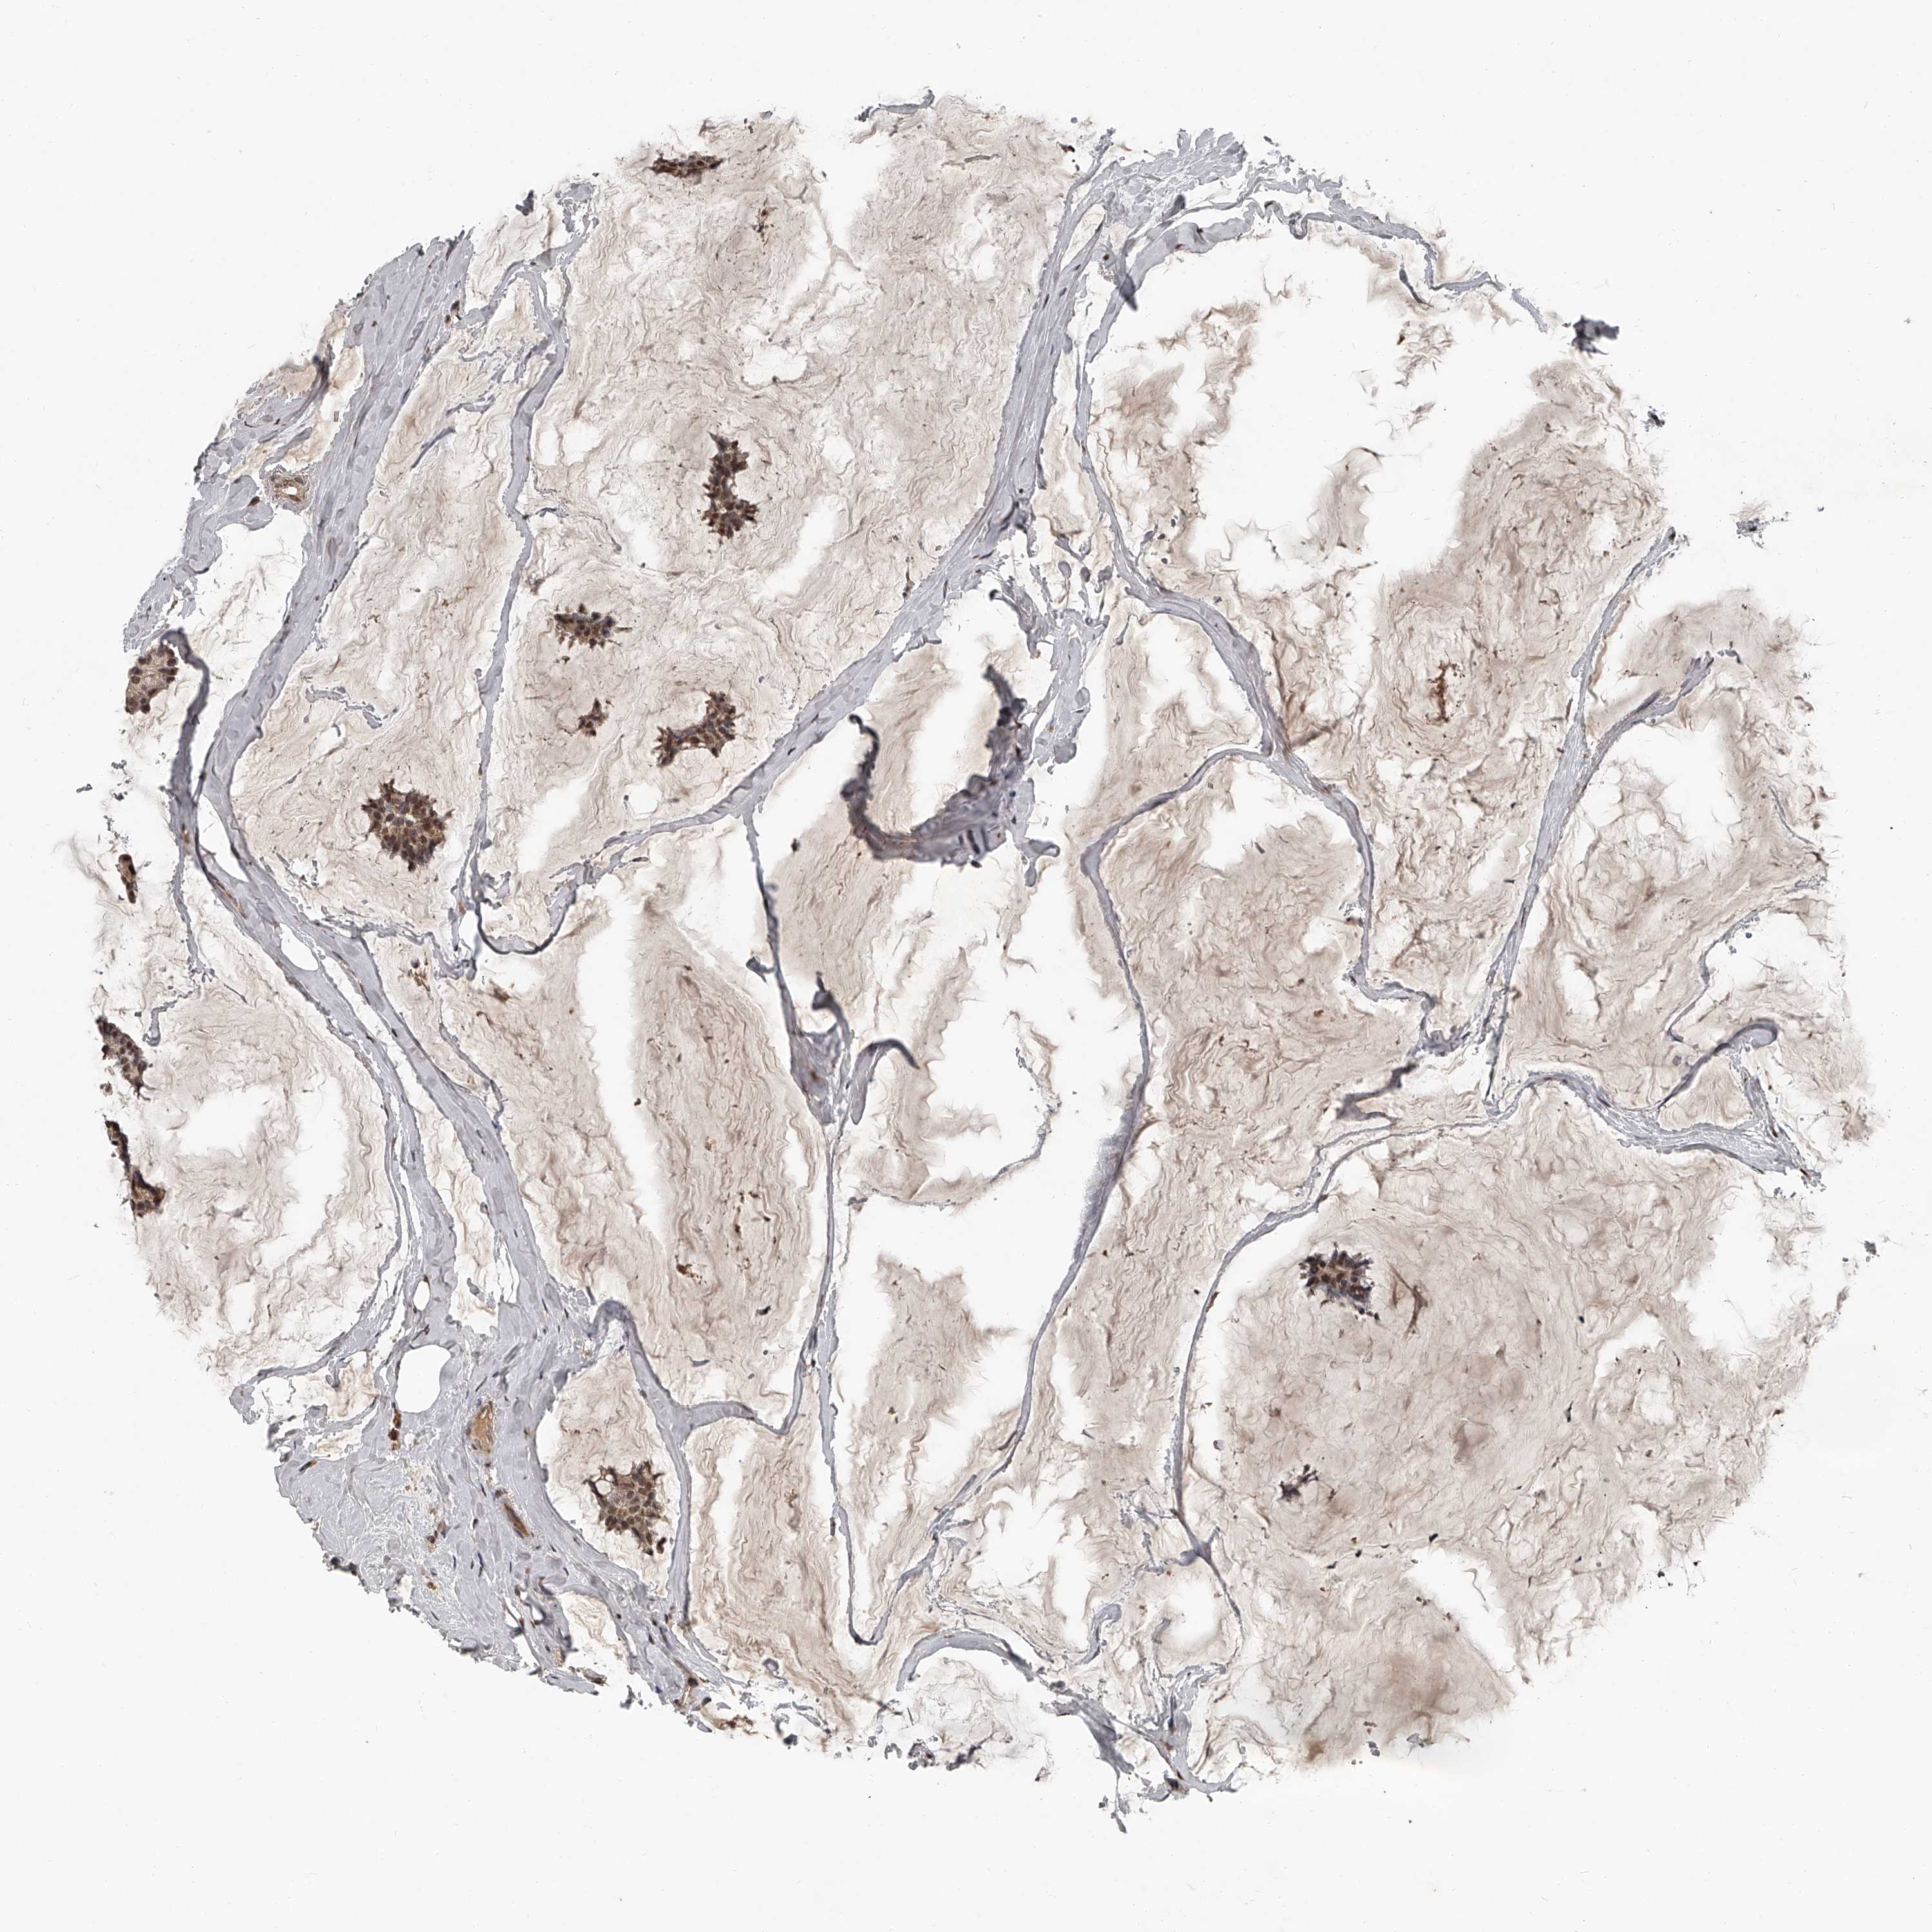

BRCA TCGA BRCA VALIDATION PROTEIN EXPRESSION